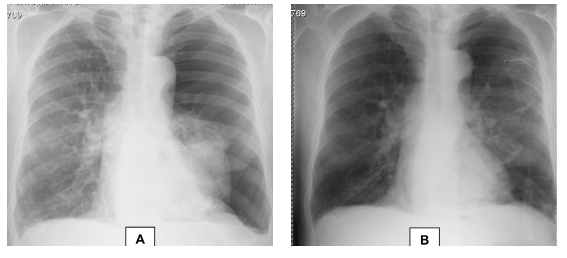

Ao 9.º dia de internamento verificouse novo agravamento clínico, com aumento da dispneia em repouso, dessaturação significativa e aumento marcado do enfisema subcutâneo. A telerradiografia torácica mostrou manutenção da câmara de pneumotórax apical à esquerda. Foi colocado novo dreno torácico (Joly n.º 18) no segundo espaço intercostal esquerdo, na linha axilar anterior (Fig. 2). Ambos os drenos ficaram funcionantes, a borbulhar com os movimentos respiratórios, tendo sido conectados a aspiração de baixa pressão. Por não melhoria clínica, com persistência de enfisema subcutâneo maciço (enfisema da face condicionando encerramento palpebral bilateral, do pescoço, do tórax e de ambos os membros superiores) e voz nasalada, foi efectuada TC torácica (Fig. 3), que mostrou enfisema subcutâneo extenso, pneumopericárdio e pneumomediastino, pneumotórax à esquerda de grau moderado, enfisema parasseptal e centrilobular difuso com bolhas apicais de grandes dimensões. Perante estes dados, foi solicitada a avaliação por Cirurgia Cardiotorácica que, dada a gravidade da DPOC, considerou que o doente não reunia as condições necessárias para ser submetido a tratamento cirúrgico.

Fig. 2 Telerradiografia torácica ao 9.º dia de internamento

Fig. 3 Corte de TC torácica